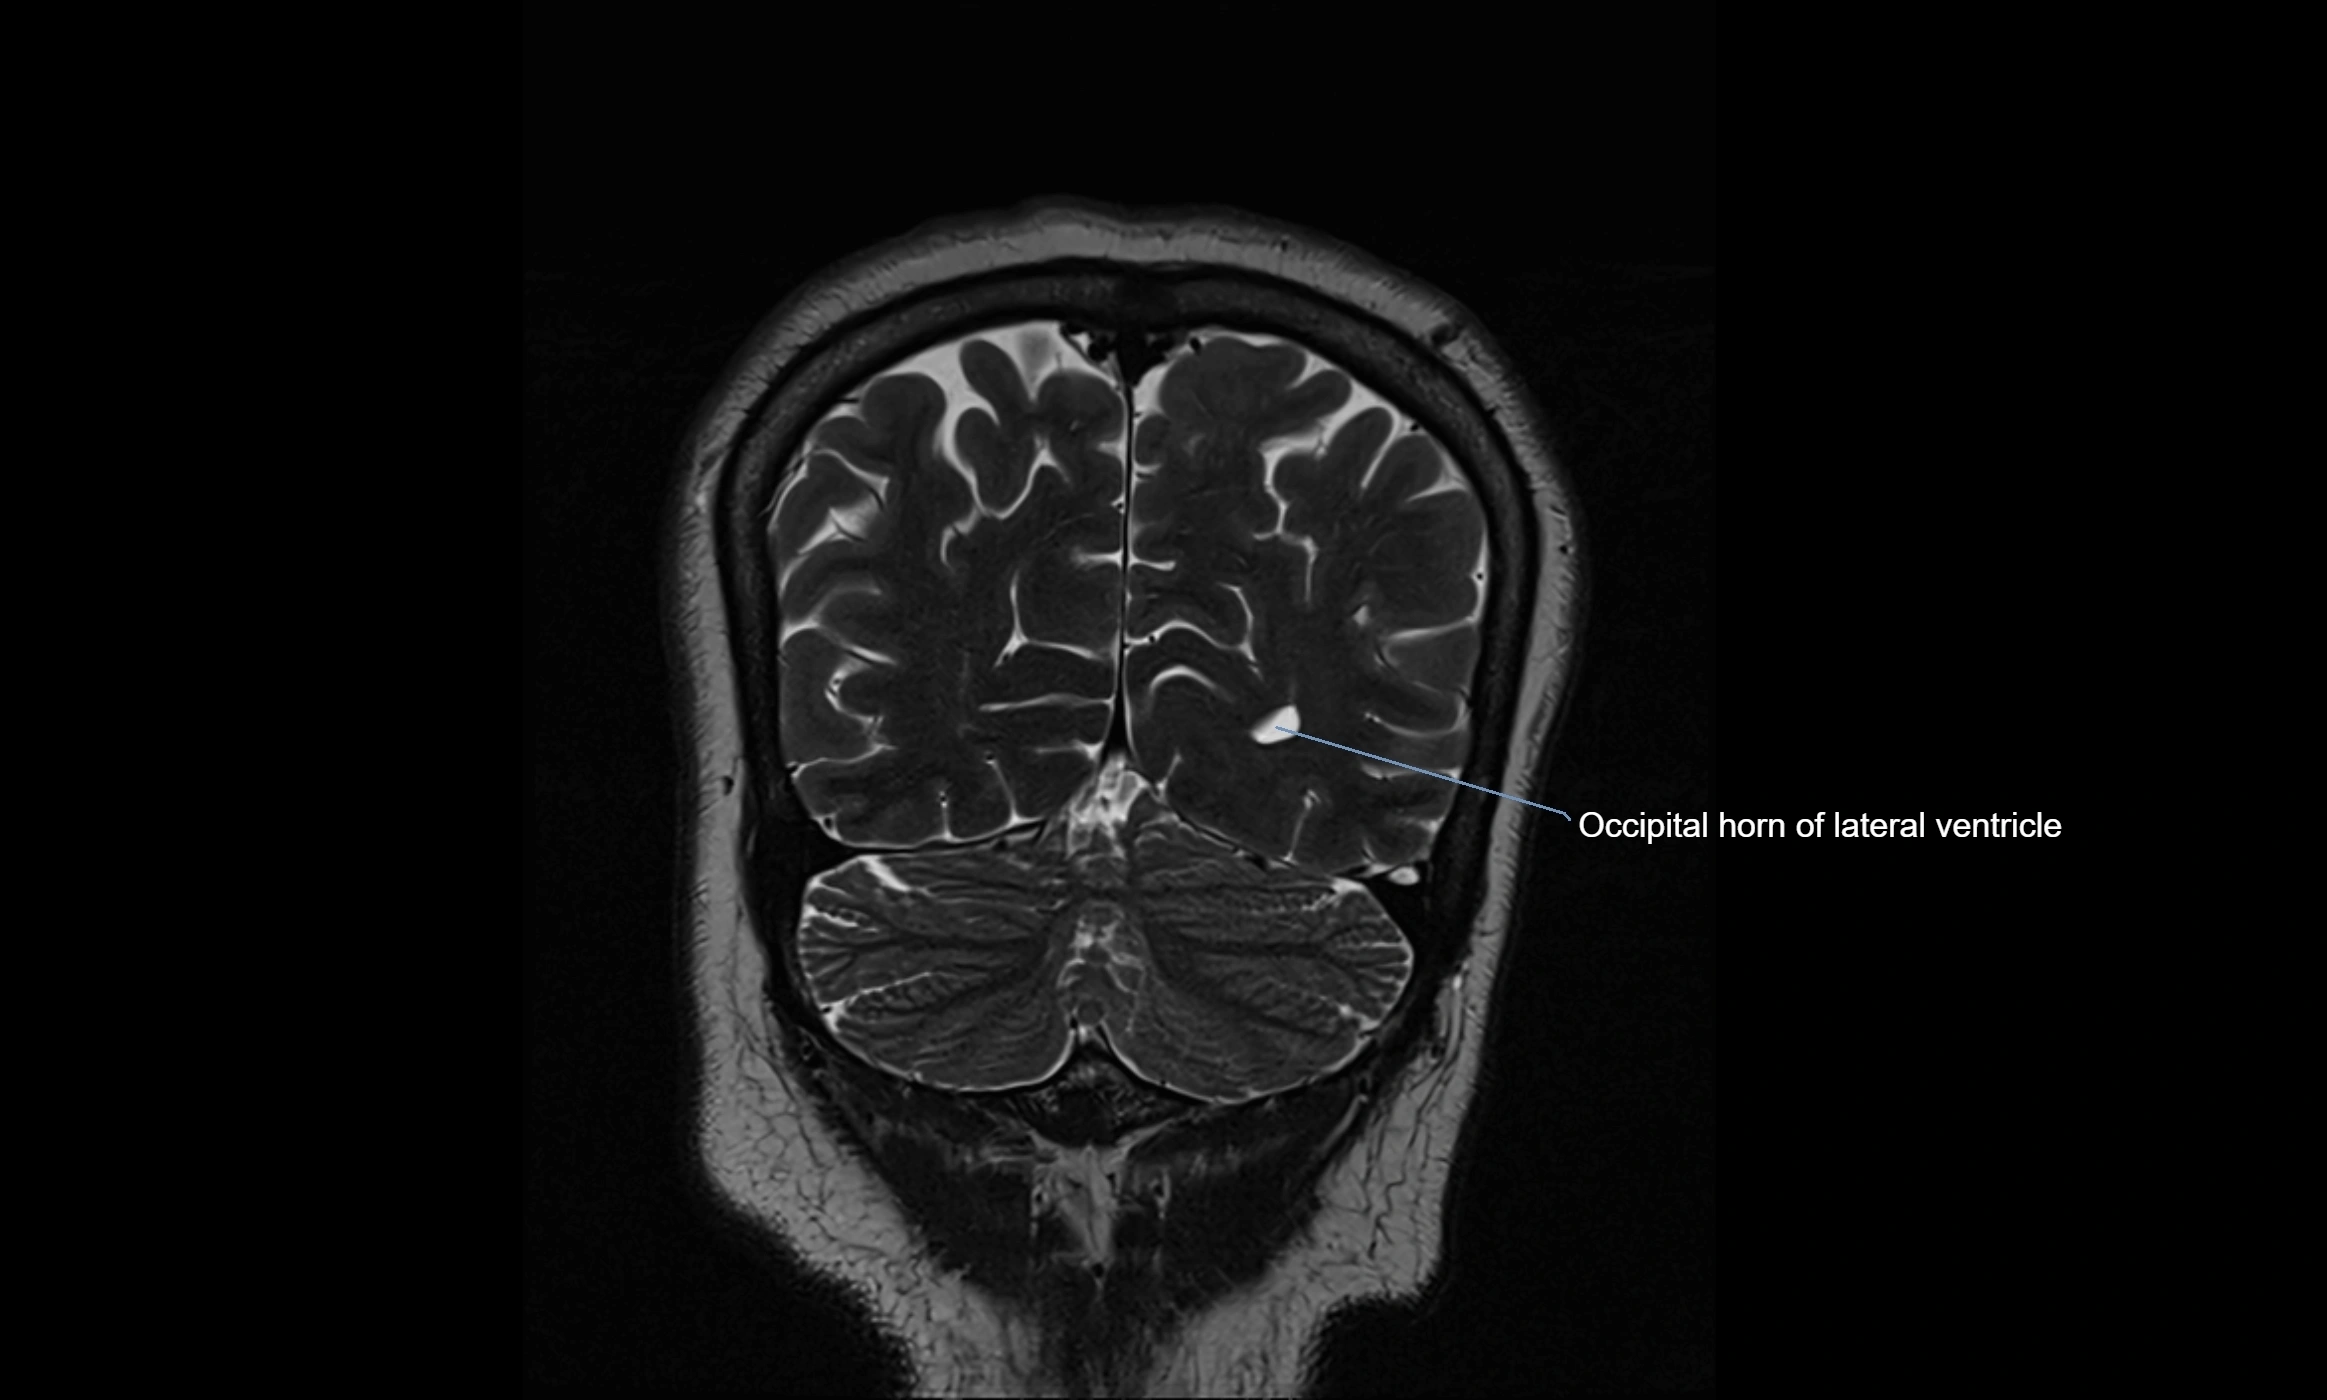

CT image

image